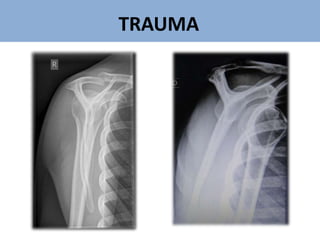

Trauma - clavícula

CLAVÍCULA

AP da clavícula

AP da clavícula com 30° caudal

AP da clavícula com 30° cefálico